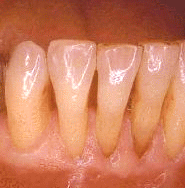

La imagen muestra la condición clínica inmediata que sigue a una incisión correcta para la  gingivectomía. La terminación  apical de la bolsa se localizó por debajo de la linea  mucogingival  y la incisión tuvo que realizarse en  mucosa móvil. En la superficie bucal del canino se observa un cálculo  subgingival que ha sido expuesto por dicha técnica quirúrgica.

El mismo paciente 10 años después del  tratamiento. El paciente fue  instruído en la higiene dental cuidadosa y la limpieza supragingival profesional se realiza una vez cada tres meses. Ninguna progresión de enfermedad periodontal ha ocurrido.